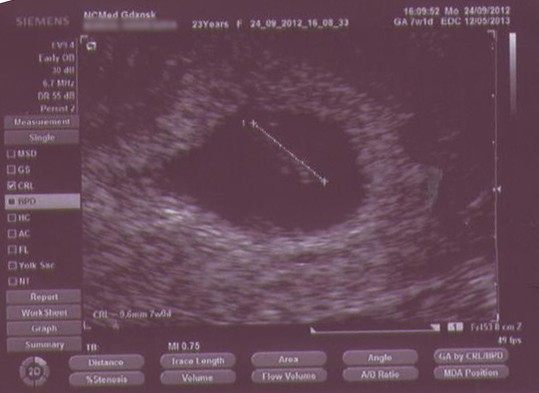

czekam na wiesci od Iownka- bo my jestesmy w identycznym czasie w ciazy![]()

I lekarz zaprosił mnie na kolejne usg między 11 a 13 tygodniem